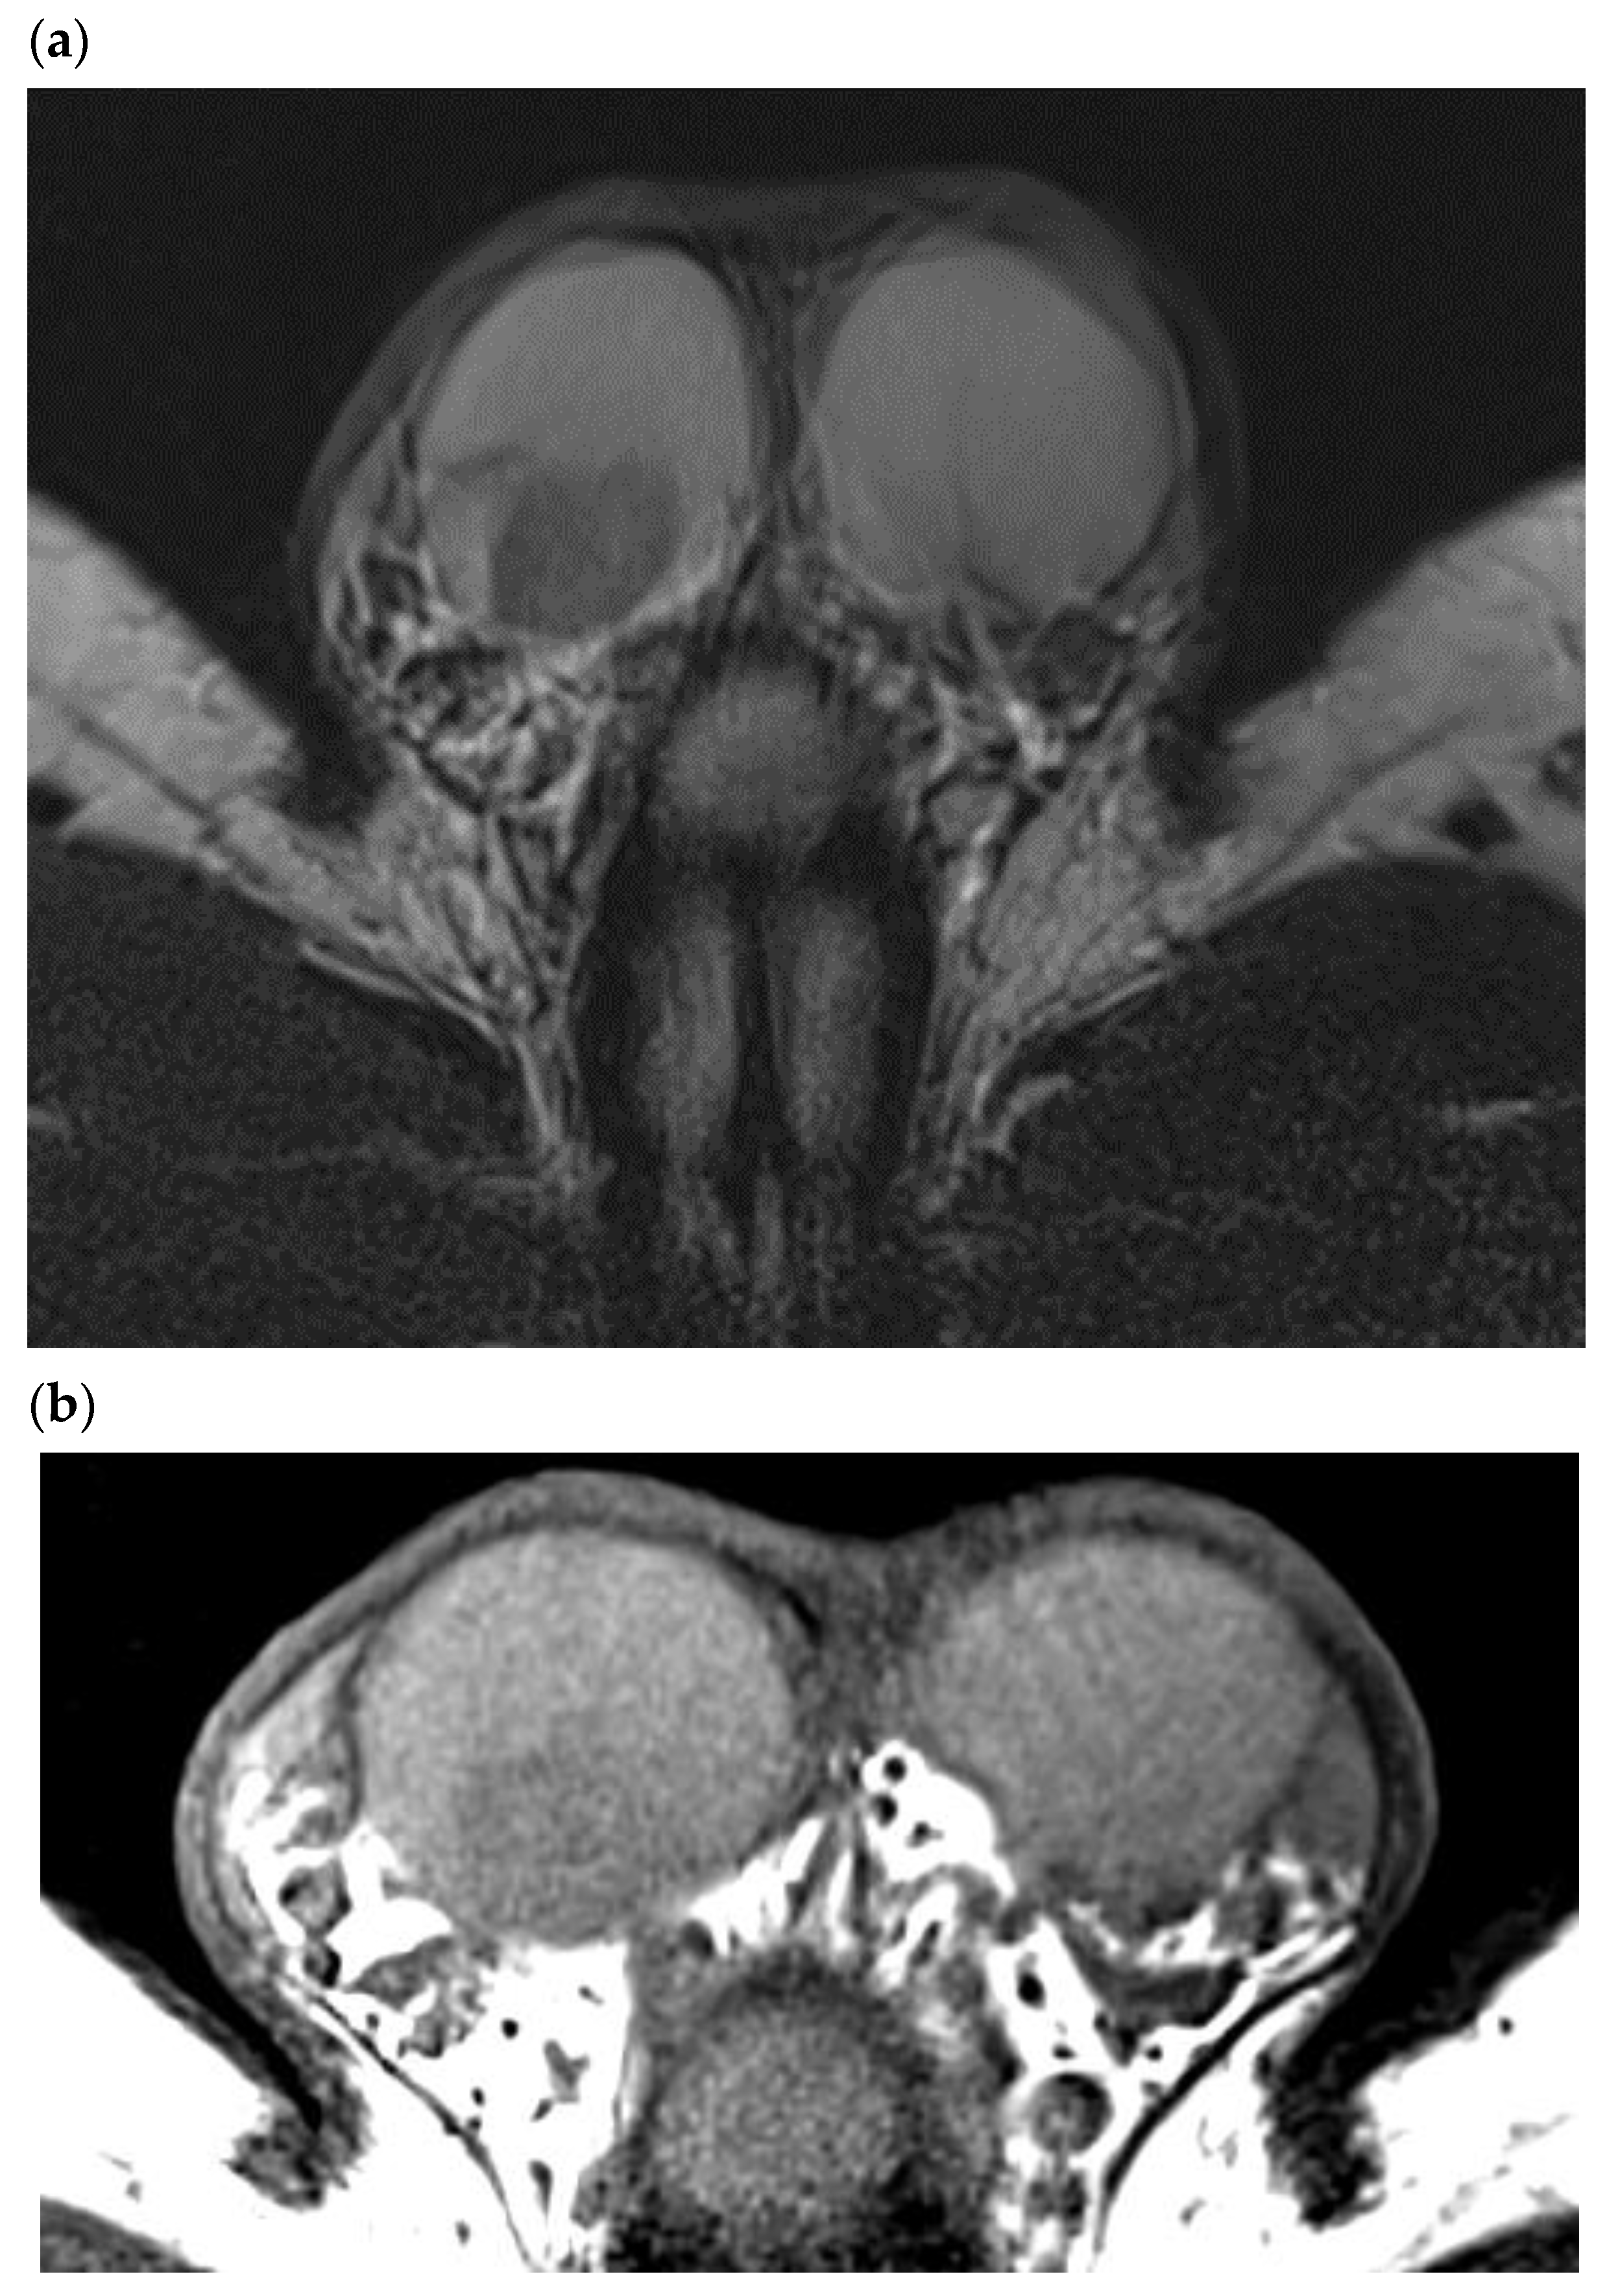

5. Leydig Cell Hyperplasia/Tumor Associated with Klinefelter Syndrome

Klinefelter syndrome (KS) or 47,XXY (gonosomal aneuploidy) affects 0.1–0.2% of the general population, but the incidence rises to 3.1% in the infertile population [34]. Patients with KS are therefore regularly encountered during an infertility work-up. The ultrasound appearance of the testicles of KS patients is characteristic, and it should alert the radiologist. Rocher et al. recorded the scrotal ultrasound exams of 67 infertile men with KS and 66 non-KS non-obstructive azoospermic men, with histological comparison [9]. The KS patients had severe testicular hypotrophy (mean testis volume 2 mL), and a coarse or micronodular (nodules < 3 mm) echotexture versus a normal/striated echotexture in the infertile non-KS patients. The KS patients presented increased bilateral and symmetrical microlithiasis, unlike the infertile non-KS patients (28% vs. 4.5%). Histology confirmed that the nodules detected in KS patients were benign LCTs associated with Leydig cell hyperplasia surrounded by Sertoli cell involution and seminiferous tubule degeneration. Some patients present with mosaic Klinefelter syndrome: an extra X chromosome in some cells with generally fewer symptoms. Our experience with mosaic Klinefelter syndrome is based on nine patients included in a series of 67 patients with KS syndrome: there were quite similar in testis volume (2 ± 0.9 mL versus 2.4 ± 1.44 mL per testis), testosterone level (10.1 ± 5.2 nmol/mL versus 11.1 ± 4.85 mL), and FSH level (33.7 ± 16.2 UI/L versus 28.9 ± 11.5 UI/L) [9]. Severe testicular hypotrophy with hypervascularized bilateral micronodules should prompt the radiologist to search for KS. Radical orchiectomy risks worsening the patient’s testosterone deprivation and should be avoided in this situation. Even though KS patients are supposed to be at risk of testicular germ cell tumors, it appears that most nodular anomalies of the testicle found in these patients are linked to Leydig cell hyperplasia/tumors (Figure 9). However, the radiologist should keep in mind that KS patients are at risk of extra gonadic germ cell tumors, especially located in the mediastinum [35].

Figure 9.

26-year-old patient addressed for infertility work up/Klinefelter’s syndrome follow up. Leydig cell hyperplasia in a patient with Klinefelter’s syndrome. (a) Two patients with major testicular hypotrophy (2 mL), with coarse echostructure and micronodules mostly hyperechoic. (b) Color Doppler ultrasound showing diffuse hypervascularization of the testicle, which contrasts with the relatively hypovascularized aspect of undescended testicles.